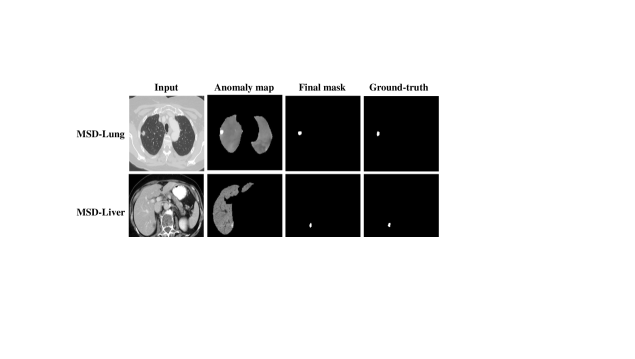

Refer to caption

Figure 7: The anomaly detection visualization of the MSD-Lung and MSD-Liver datasets.

4.3.2 Anomaly Detection.

We utilize MedDiff-FM to accomplish the anomaly detection task on the MSD-Lung and MSD-Liver datasets. Since we employ anatomical structure masks to focus on specific anatomical regions, we exclude lesions that are not located within the liver or lung regions segmented by TotalSegmentator  [61]. We provide the results of fully supervised learning using nnU-Net [20] on the test set for reference. Table 5 demonstrates the anomaly detection results. The number in parentheses represents the diffusion steps. MedDiff-FM employs Gaussian noise, and when adding noise to unhealthy CT images, small time steps struggle to disrupt tumor structures [64]. The results indicate that utilizing MedDiff-FM for anomaly detection in CT images can achieve excellent performance. Fig. 7 visualizes the anomaly detection results, where MedDiff-FM successfully detects the lung and liver tumors.